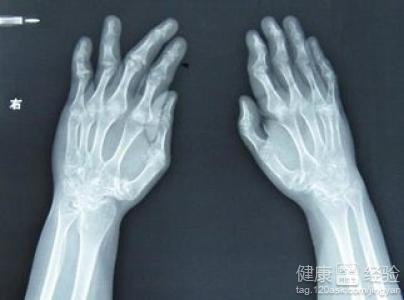

高尿酸血症患者吃什麼好

1其實痛風就是一種吃出來的疾病。痛風被現代人稱為"富貴病",痛風時一個長期的慢性的疾病,痛風其實和我們日常生活的飲食習慣等方面時離不開的。痛風其實就是長期的尿酸偏高造成的疾病。尿酸越高,得痛風的可能性就越大。

2痛風既然是富貴病,那麼在平時的飲食習慣中,應當的減少食用高嘌呤的食物,比如海鮮、魚肉、豬肉、豆類的食物,或者是花菜、菠菜等食物也是需要盡量避免食用。從飲食習慣中改善,才能避免痛風的兵病發。